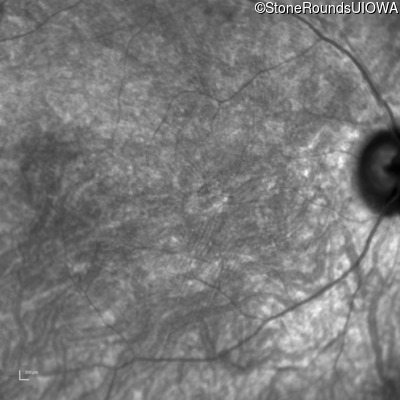

Infrared Fundus Photograph - Right - 20/200 +2

Exemplar